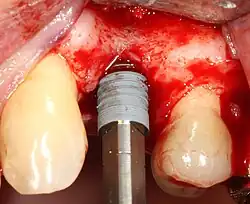

Основная операция по имплантации

Разборный имплантат состоит из непосредственно имплантата и надстройки (супраструктуры), именуемой абатментом. Такой имплантат может быть установлен по одно- и двухэтапному протоколу. Двухэтапный протокол подразумевает полное погружение имплантата и накрывание его слизистой оболочкой, в результате чего исключается любой контакт имплантата с полостью рта — эта процедура называется первым этапом дентальной имплантации. Второй этап заключается в установке какой-либо надстройки (супраструктуры) — это может быть как формирователь десны, так и абатмент с временной коронкой или другим видом протезной конструкции. После какого промежутка времени будет выполнен второй этап обычно решает имплантолог, опираясь на данные о качестве костной ткани, возраст и общее состояние пациента, а также свой клинический опыт. Классические сроки составляют 4—6 месяцев, однако последнее время существует тенденция к сокращению сроков ожидания до 2,5—3 месяцев. Это связано с лучшим пониманием процесса остеоинтеграции, а также оптимизацией макродизайна и микрохарактеристик поверхности имплантатов.

В неразборном имплантате (употребляются также термины: одноэтапный имплантат, моноимплантат) внутрикостная часть имплантата и абатмент обычно изготовлены из единого куска материала. После установки имплантат своей наддесневой частью сразу оказываются в контакте с полостью рта. На усмотрение доктора устанавливается формирователь десны либо временная коронка. В случае установки временной протезной конструкции (коронки, моста или полного протеза) на имплантат не позднее трёх дней после имплантации говорят о немедленной нагрузке.